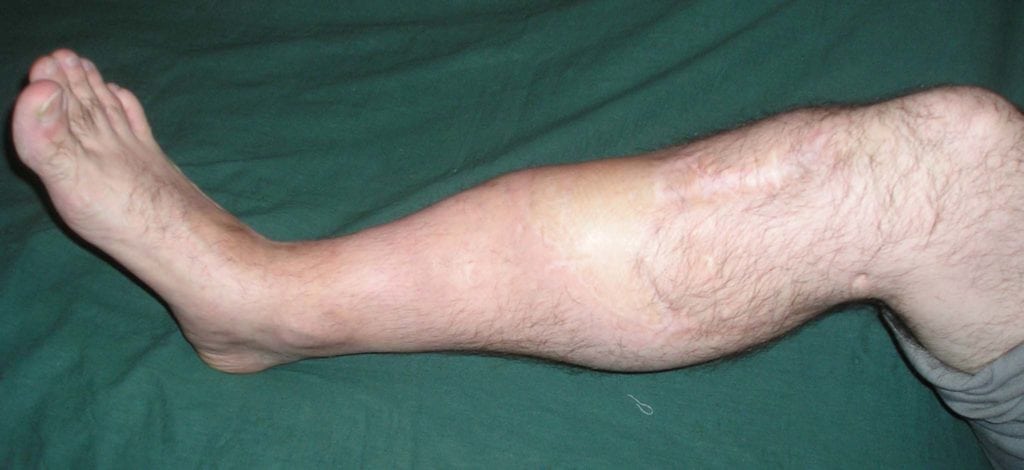

Больные с псевдоартрозом практически всегда жалуются на открытые или закрытые переломы в анамнезе. На протяжении многих месяцев после травмы их беспокоит постоянная боль, аномальная подвижность кости и характерные щелчки при движениях. Если ложный сустав локализуется на нижней конечности, больному становится трудно ходить и вести привычный образ жизни.

Отсутствие квалифицированной медицинской помощи может иметь для человека ужасные последствия. В лучшем случае его будут беспокоить постоянные боли, а функция конечности останется нарушенной. В худшем у больного разовьется выраженная деформация ноги или руки, что приведет к инвалидности.